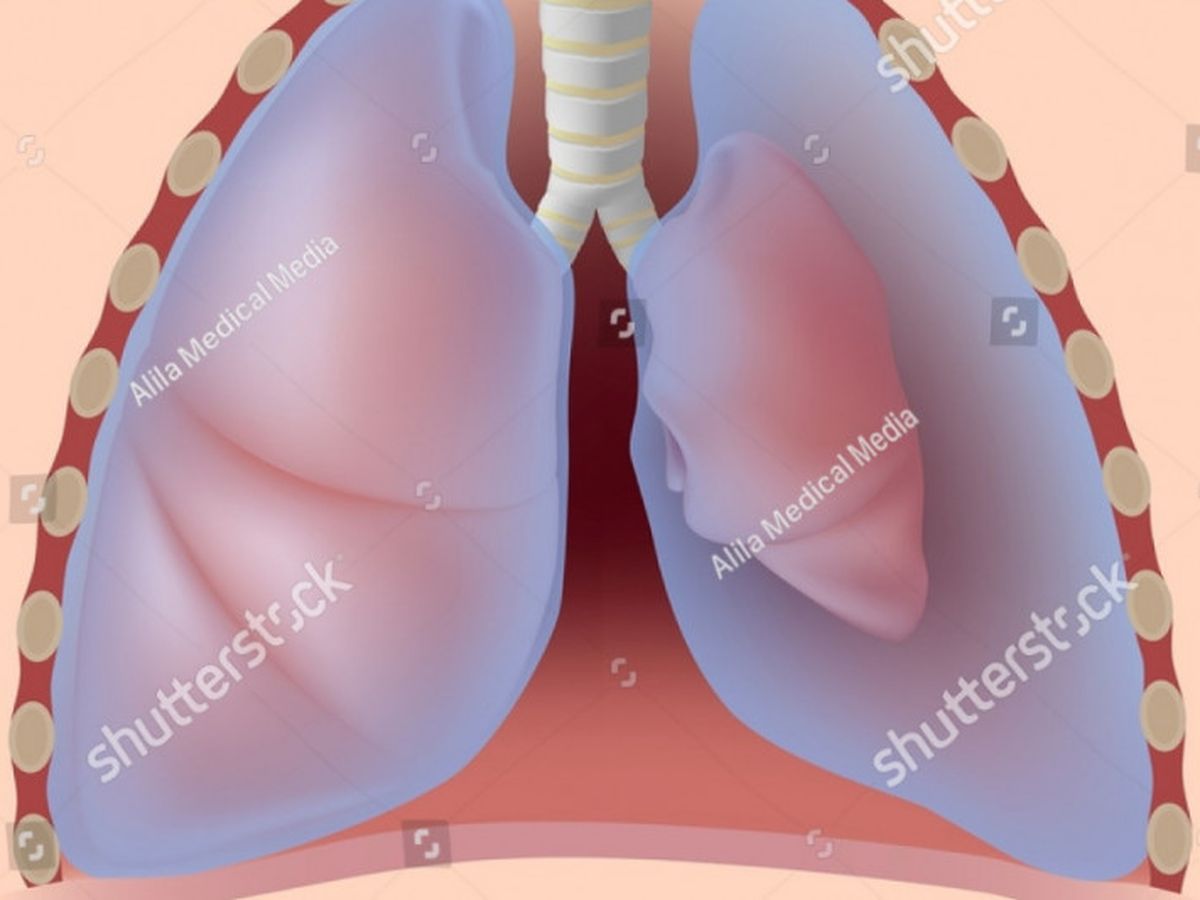

Hello. My name is Matthew, and my father is currently in the Intensive Care unit in Anderson Hospital. He has two collapsed lungs.

We started noticing problems two days ago, when he began complaining of shortness of breath. This came to a head last night (10/16) around midnight, when he tried to lay down. He became completely incapable of drawing a breath, and his skin was ice cold to the touch. We rushed him to the local ER, where he was diagnosed and a pair of tubes inserted between his ribs to alleviate some of the pressure on his lungs. He was sent from there to Anderson, where he is currently in ICU.

We started noticing problems two days ago, when he began complaining of shortness of breath. This came to a head last night (10/16) around midnight, when he tried to lay down. He became completely incapable of drawing a breath, and his skin was ice cold to the touch. We rushed him to the local ER, where he was diagnosed and a pair of tubes inserted between his ribs to alleviate some of the pressure on his lungs. He was sent from there to Anderson, where he is currently in ICU.